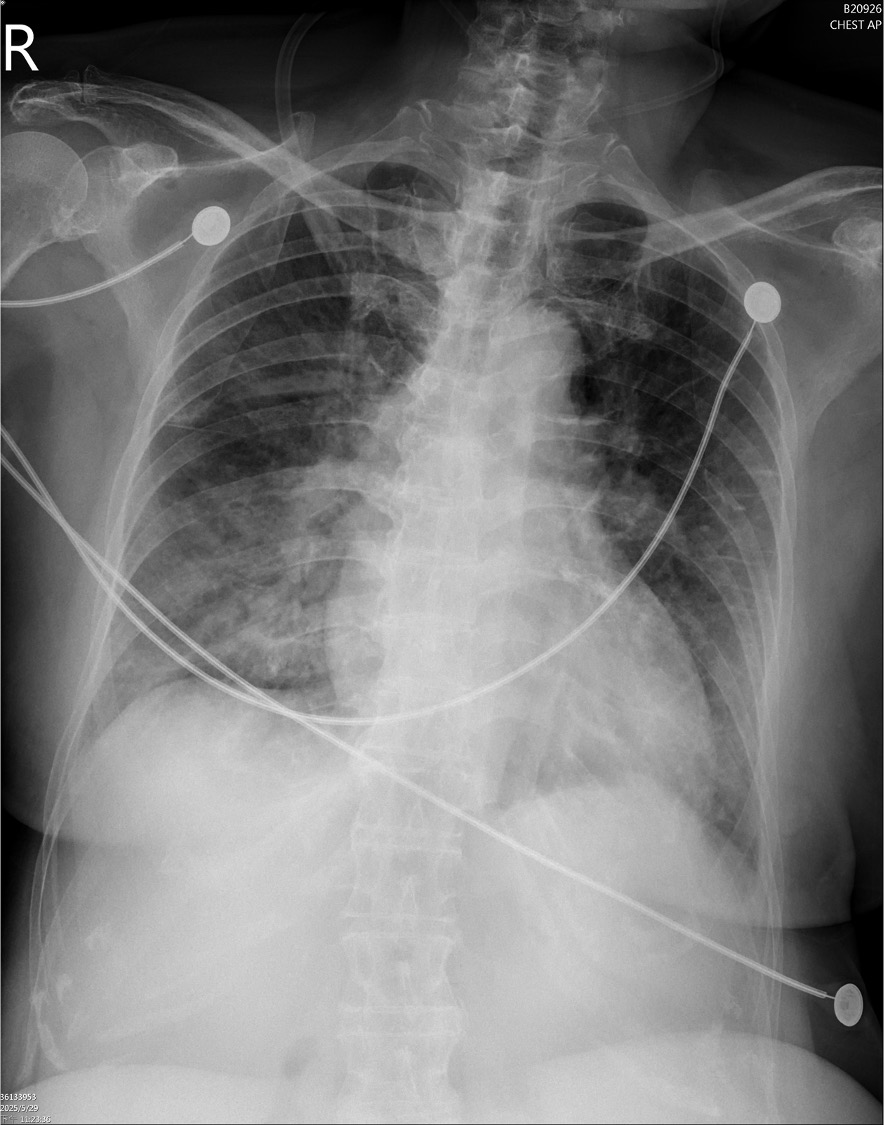

ECG showed ST elevation in aVR with diffuse ST depression. Chest X-ray revealed bilateral pulmonary edema. Laboratory data demonstrated elevated hs-troponin I (1012 pg/mL). Bedside TTE revealed global hypokinesis with an estimated LVEF of 40%.